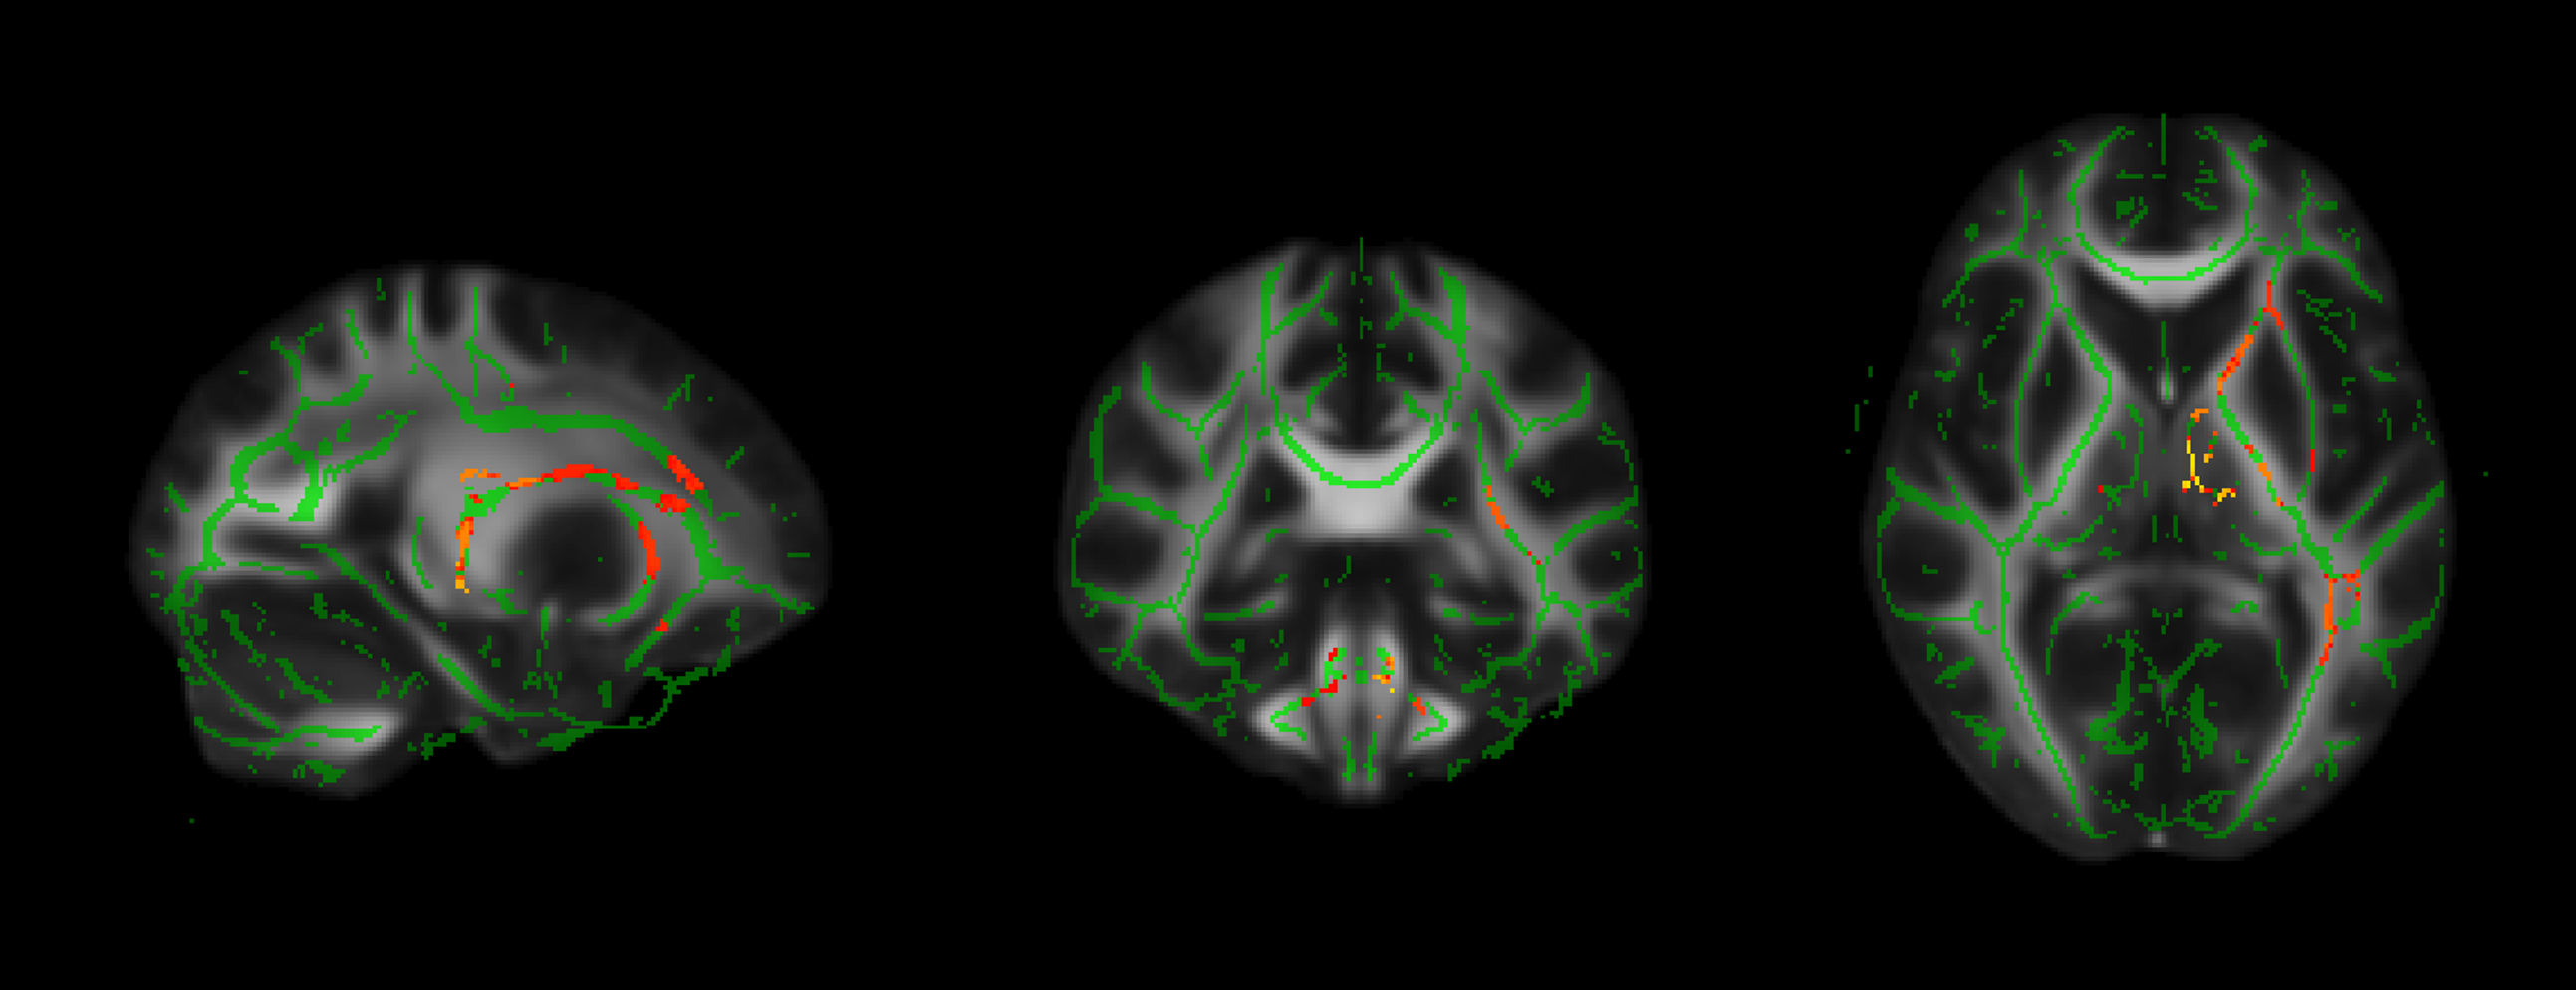

研究團隊發現,細懸浮微粒與二氧化氮濃度減少與老年人的注意力提升呈正相關。更重要的是,磁振造影顯示這些污染物濃度下降,與多個掌管注意力與記憶力的大腦白質區域結構完整性有密切相關。

PM2.5降低幅度越大與大腦顯著相關的區域,紅黃色為統計顯著區域